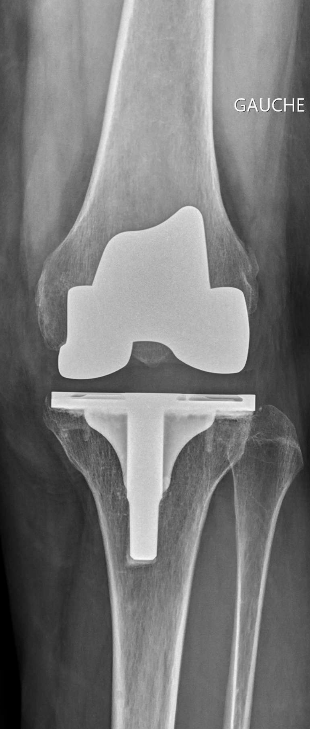

La prothèse totale de genou vise à remplacer l’articulation du genou. Elle est composée d’une pièce fémorale et tibiale métalliques mises en place sur le fémur distal et dans le tibia proximal.

Une pièce intermédiaire en polyéthylène est interposée entre les composants fémoraux et tibiaux.

En fonction des cas, la surface articulaire rotulienne peut être remplacée ou non par un implant en polyéthylène.

La fixation des implants peut se faire soit avec du ciment chirurgical soit à l’aide d’un traitement de surface prothétique favorisant la repousse osseuse.